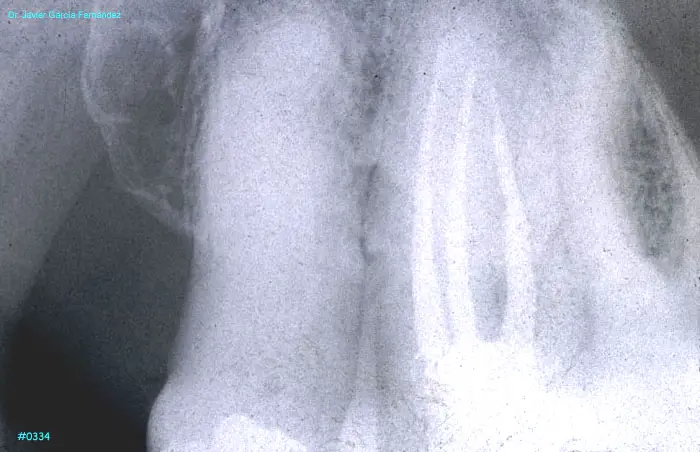

ATLAS DE CIRUGIA PERIODONTAL